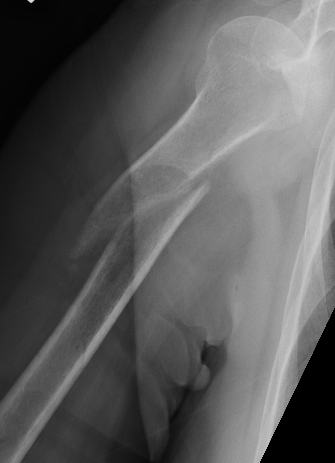

Holstein Lewis fracture

Holstein Lewis fractureHolstein Lewis

Holstein-Lewis JBJS Am 1963

- series of 7 oblique distal third fractures with radial nerve injury

- all were treated operatively

- nerve in fracture gap in 2 / impaled in 1 / severed in 2 / contused +/- in callus in 2

- advised against attempted closed reduction

- risk of contusing nerve between fragments

- advised early open reduction through anterolateral approach

- the radial nerve is closely assoicated with the fracture site and the fracture spike